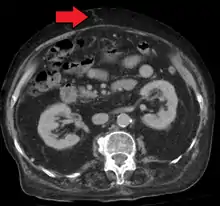

Mark.png.webp)

Ultrasonography (US) is the first-line imaging technique for the diagnosis and follow-up of portal hypertension because it is non-invasive, low-cost and can be performed on-site.[17]

A dilated portal vein (diameter of greater than 13 or 15 mm) is a sign of portal hypertension, with a sensitivity estimated at 12.5% or 40%.[18] On Doppler ultrasonography, a slow velocity of <16 cm/s in addition to dilatation in the main portal vein are diagnostic of portal hypertension.[19] Other signs of portal hypertension on ultrasound include a portal flow mean velocity of less than 12 cm/s, porto–systemic collateral veins (patent paraumbilical vein, spleno–renal collaterals and dilated left and short gastric veins), splenomegaly and signs of cirrhosis (including nodularity of the liver surface).[17]

The hepatic venous pressure gradient (HVPG) measurement has been accepted as the gold standard for assessing the severity of portal hypertension. Portal hypertension is defined as HVPG greater than or equal to 5 mmHg and is considered to be clinically significant when HVPG exceeds 10 to 12 mmHg.[20]